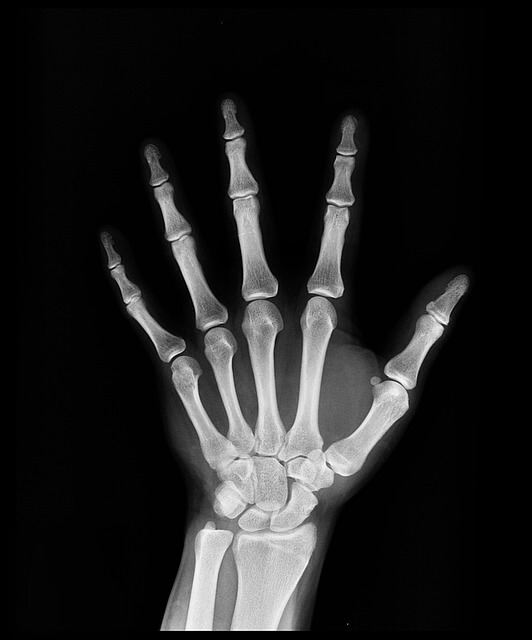

스마트폰·컴퓨터 사용, 가사노동(청소·조리) 등 손을 많이 쓰는 생활 습관은 손 관절에 부담을 줍니다. 단순한 피로로 여겨 방치하기 쉽지만, 증상이 악화되면 관절 변형으로까지 이어질 수 있습니다.

손가락 관절 통증의 흔한 원인으로는 퇴행성 관절염과 건초염이 있습니다.

- 퇴행성 관절염: 관절 연골이 점차 손상되어 마찰이 증가하고 통증이 발생합니다.

- 건초염: 손가락 힘줄을 감싸는 막(건초)에 염증이 생겨 움직일 때 통증과 붓기가 나타납니다.